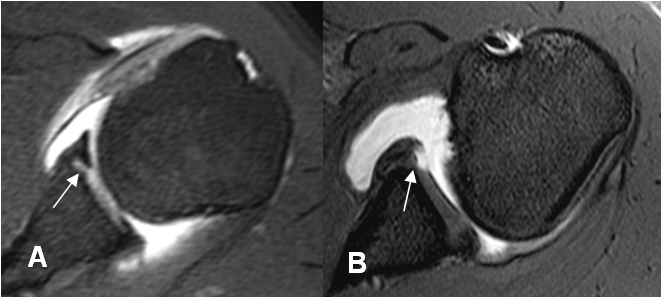

Fig 62. Lesión de Bankart.

A y B: RM axial en FFE. Alteración en la parte antero-inferior del labrum por lesión de Bankart.